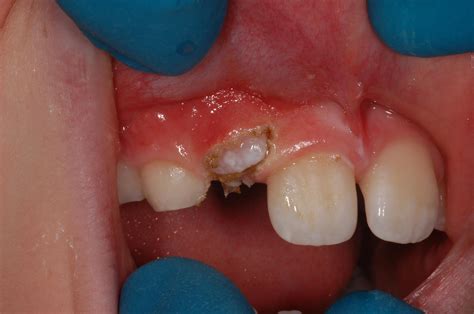

When the tooth is stuck in the bone, an oral surgeon performs an exposure procedure. This involves making a small incision in the gum to uncover the crown of the impacted canine tooth. Once the tooth is accessible, an orthodontic bracket and a small gold chain are typically attached to it. The orthodontist then uses this chain to apply gentle, continuous pressure, gradually guiding the tooth down into its designated space within the dental arch over several months.